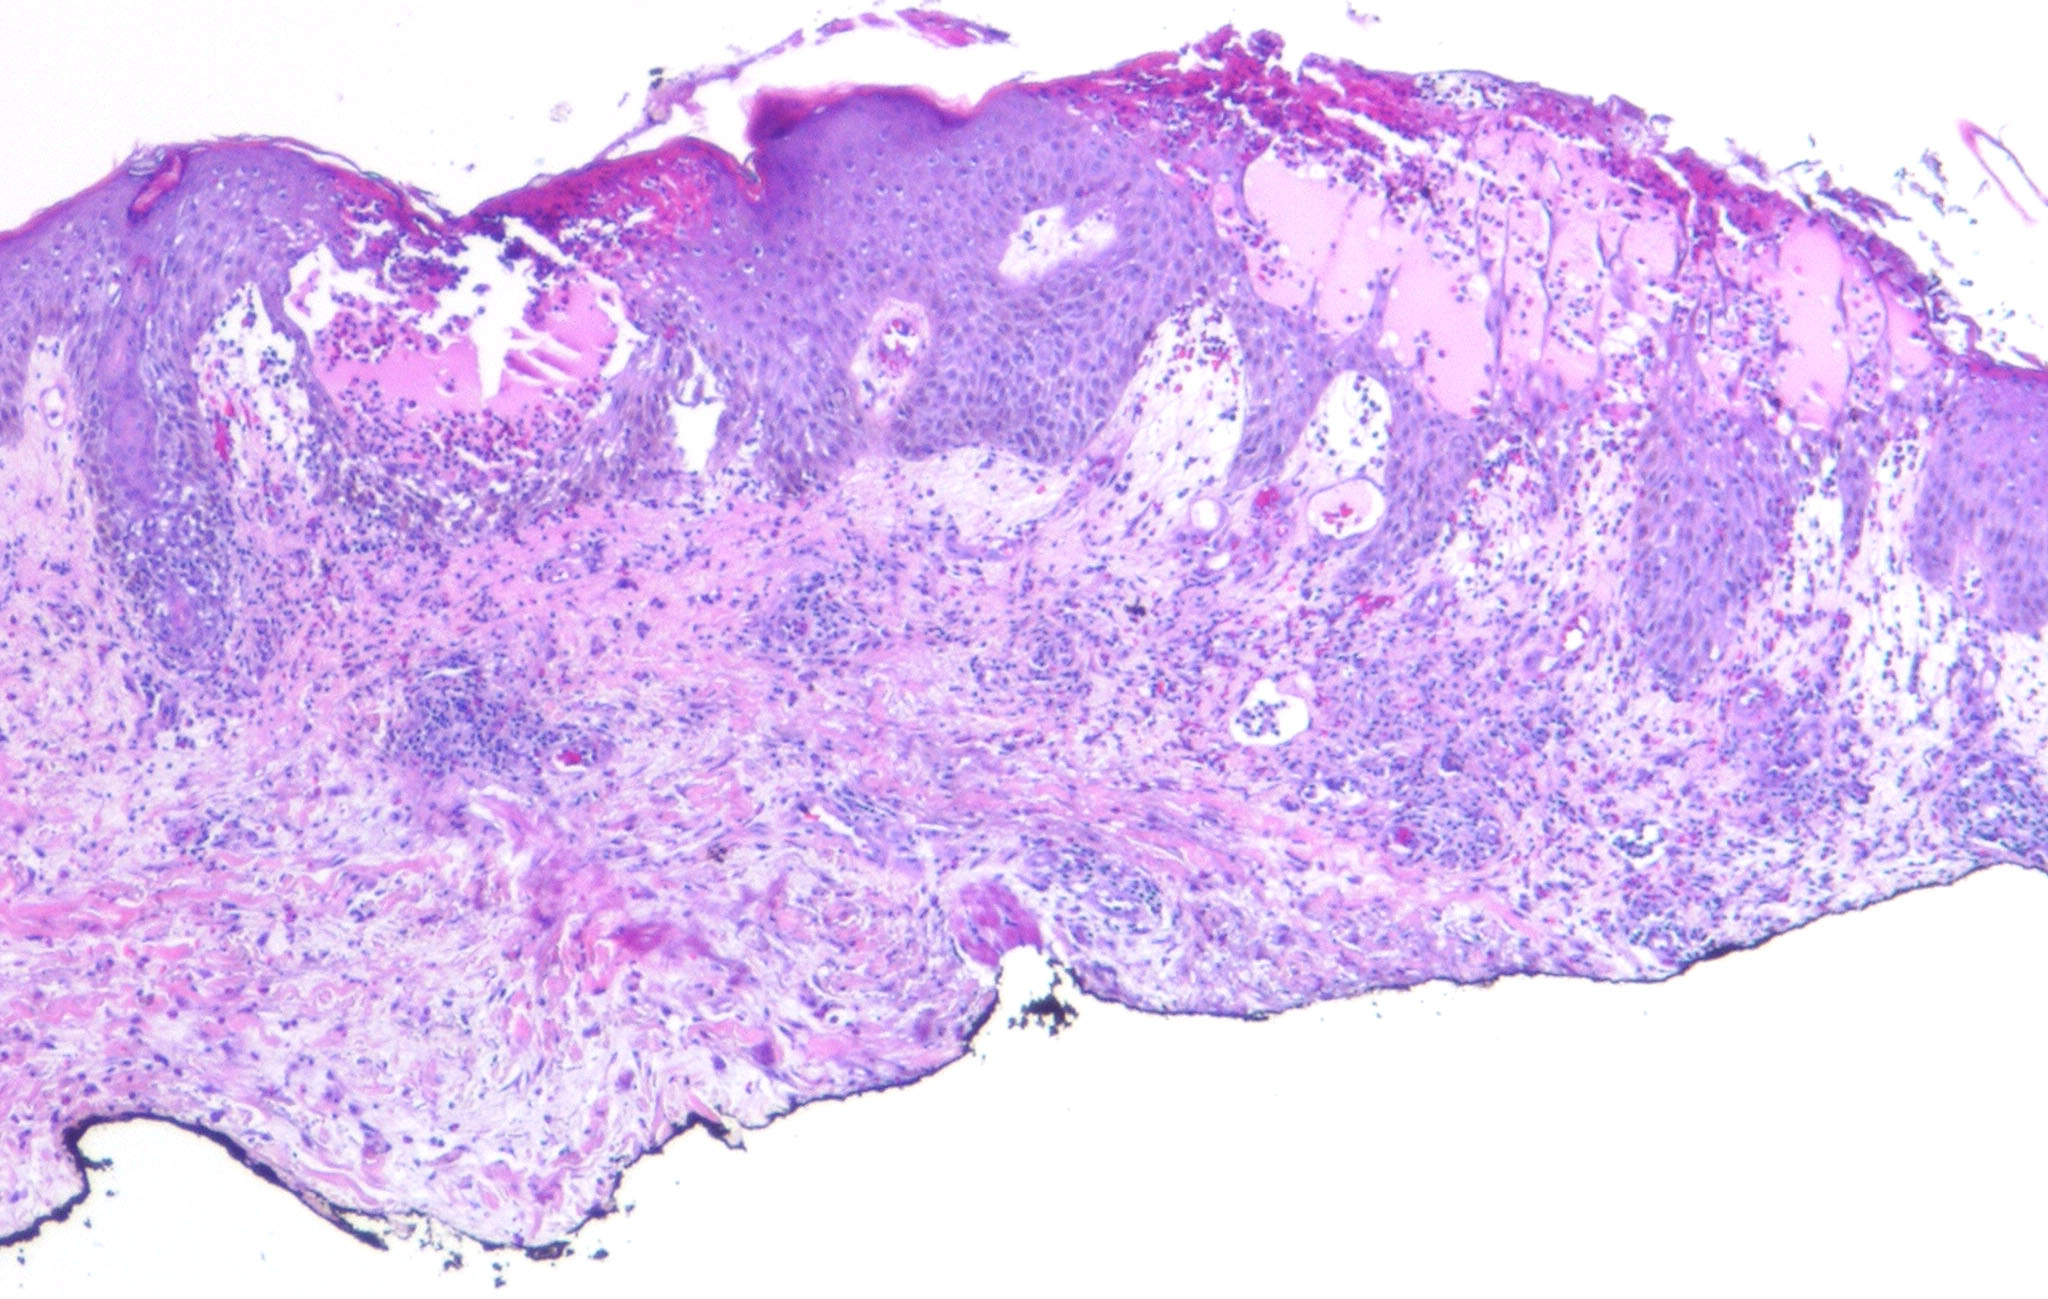

Acute contact dermatitis = التهاب ا لجلدالحاد بالتماس